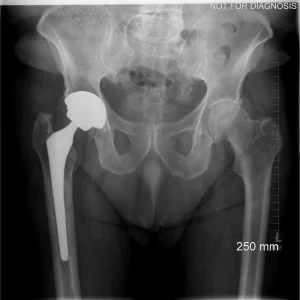

Revision Total Hip Replacement (Revision THA)

What Is a Revision Total Hip Replacement?

A revision total hip replacement (revision THA) is a surgical procedure performed to replace or repair a previous hip replacement that is no longer functioning well.

Clinical View